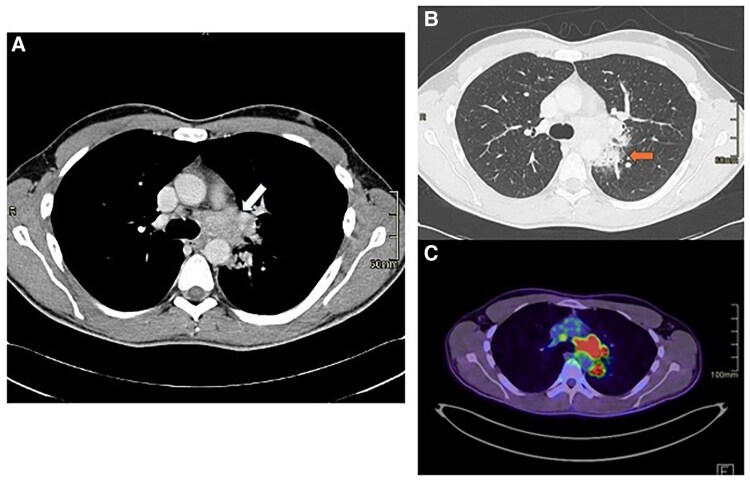

Case summary: We herein report the case of a 33-year-old male patient who presented to the Emergency Department with fever and chest pain after returning from a journey from a tropical region in Centre America. Initial tests showed elevated high-sensitivity troponin T (Hs-TnT) levels, suggesting possible cardiac involvement, but EKG and chest X-ray were normal. Echocardiography detected hypokinesis of the interventricular septum and a small pericardial effusion. Cardiac magnetic resonance (CMR) showed left ventricular function at lower normal limits and a small pericardial effusion, but also masses in the lungs and mediastinum, confirmed by computed tomography. Biopsy was performed, and histology revealed disseminated histoplasmosis. The patient was treated with antifungals and was discharged after two weeks, continuing antifungal administration in the outpatient clinic for 18 months. Follow-up imaging showed significant reduction of the masses. The patient remained asymptomatic with no further treatment needed.

Discussion: In this case report, we emphasize the essential role of a multimodal imaging approach in diagnosing cardiac inflammatory diseases. CMR was pivotal providing a three-dimensional perspective of the mediastinum, which led to the identification of a retrocardiac mediastinal mass that might have otherwise gone undetected. This highlights the importance of integrating multimodality imaging techniques to improve diagnostic accuracy and guide effective treatment strategies.